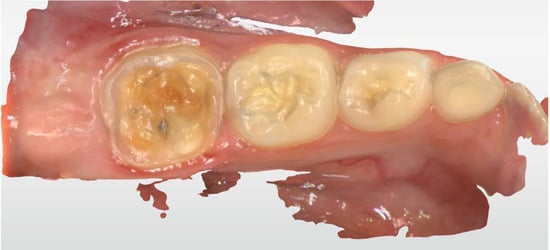

2.2. Clinical Case